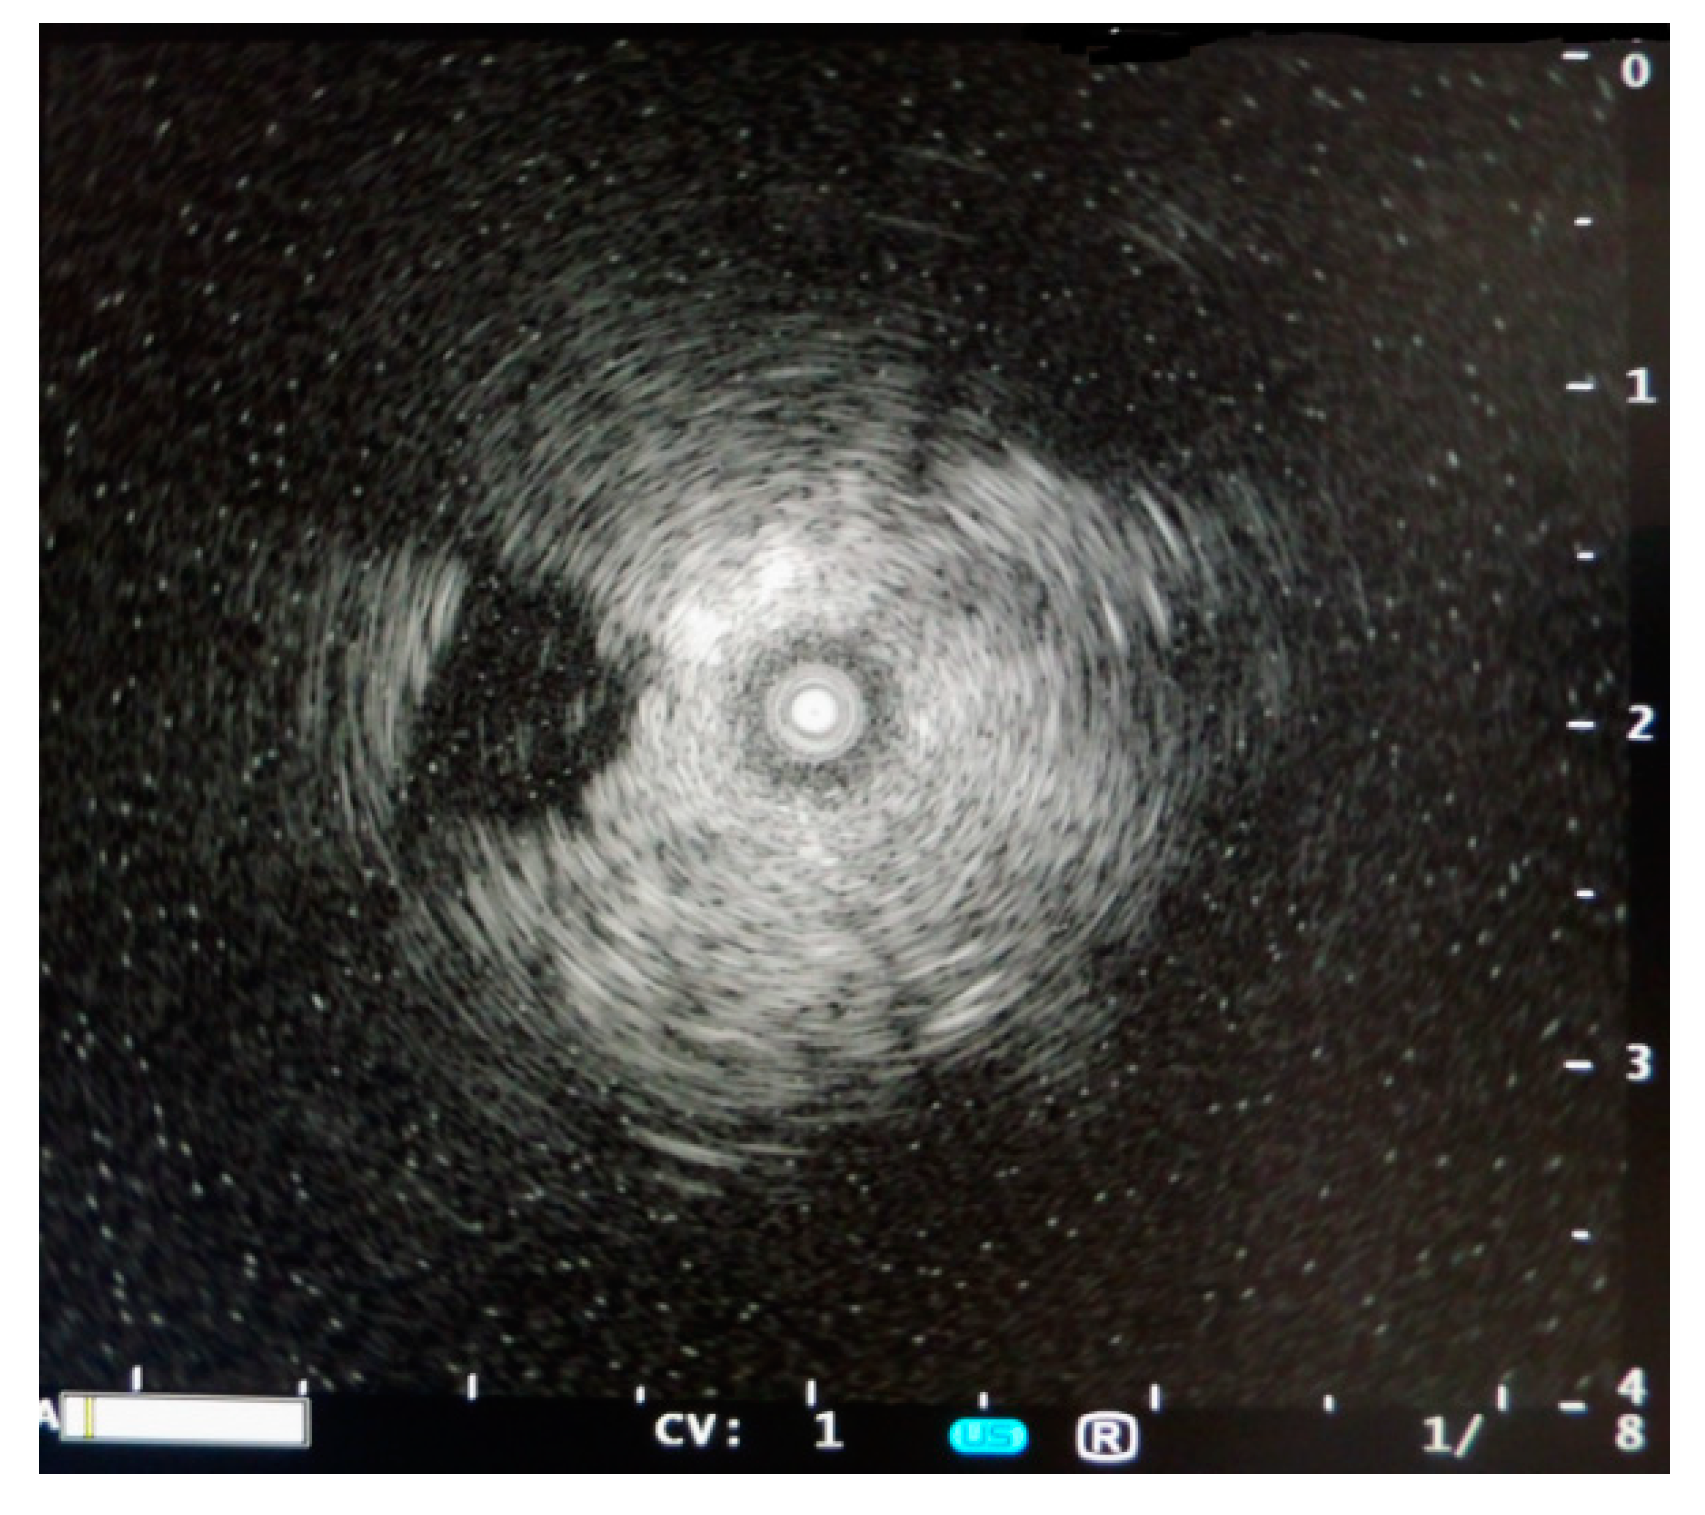

During stable flooding in-vivo with saline, unimpaired imaging without remaining air was achieved. The lung parenchyma appears homogeneous with enhanced echogenicity, where vessels and bronchi are well demarked as hypoechoic structures [18]. Trans-pulmonary imaging visualized adjacent organs such as the liver or heart (Figure 4). Doppler imaging in flooded lung is feasible and useful to detect vessels (Figure 5). No limitations regarding penetration depth were documented. High frequency linear probes (10–15 MHz) were recommended for high resolution imaging such as for small bronchi or vessels [22] (Figure 6). Using ex-vivo models and simulated intra-pulmonary nodules in-vivo, a reliable nodule detection of primary lung cancer as well as metastases were found. The tumor mass appears hypoechoic, surrounded by hyperechoic flooded lung, resulting in a high detection rate of about 100% of malignant pulmonary nodules (Figure 7), as well as simulated nodules [31]. Interestingly, the visualization is aggravated only for the bronchoalveolar cell carcinoma. The specific growth along the alveolar surface caused an echo-enhanced appearance with similar characteristics to flooded lung parenchyma [18].

Figure 7. Endobronchial sonographic imaging of intrapulmonary nodal metastasis in saline flooded lung using ex-vivo human lung models.